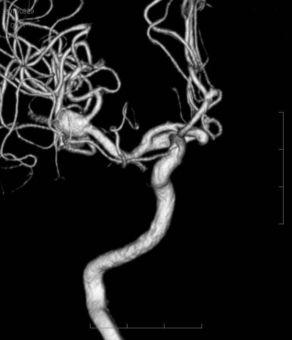

01 脳動脈瘤 開頭クリッピング術

脳動脈瘤(のうどうみゃくりゅう)とは?

脳の血管の一部が膨らんで、風船のような状態になったものです。

破裂すると “くも膜下出血” になります。

開頭 脳動脈瘤頚部クリッピング術

頭蓋骨を一部外して、脳のすき間を分け、クリップで瘤を挟んで治します。

02 脳動脈瘤 血管内コイル塞栓術

血管内コイル塞栓(そくせん)術

血管の中から瘤内にコイルを詰めて治します。 “切らずに” 治すカテーテル治療です。